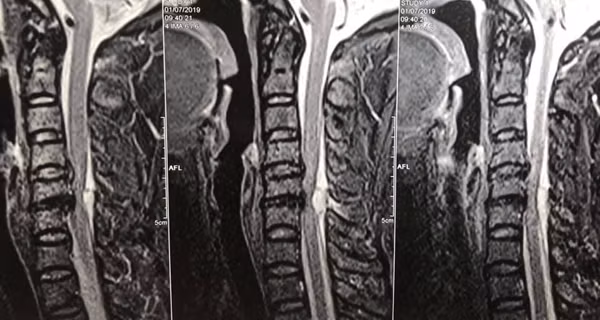

Bệnh nhân được gia đình khẩn trương đưa đi cấp cứu tại bệnh viện tỉnh và kết nối đến BS để chuyển thẳng lên Việt Đức. BS Trần Quốc Khánh cho biết: “Qua thăm khám, và kết quả chụp cộng hưởng từ cấp cứu để tìm kiếm nguyên nhân, cho thấy bệnh nhân có một khối máu tụ rất to đang chèn ép nặng cột sống cổ, đó chính là nguyên nhân gây liệt hai chân”.

| Hình ảnh chụp cộng hưởng từ cho thấy khối máu tụ chèn ép |